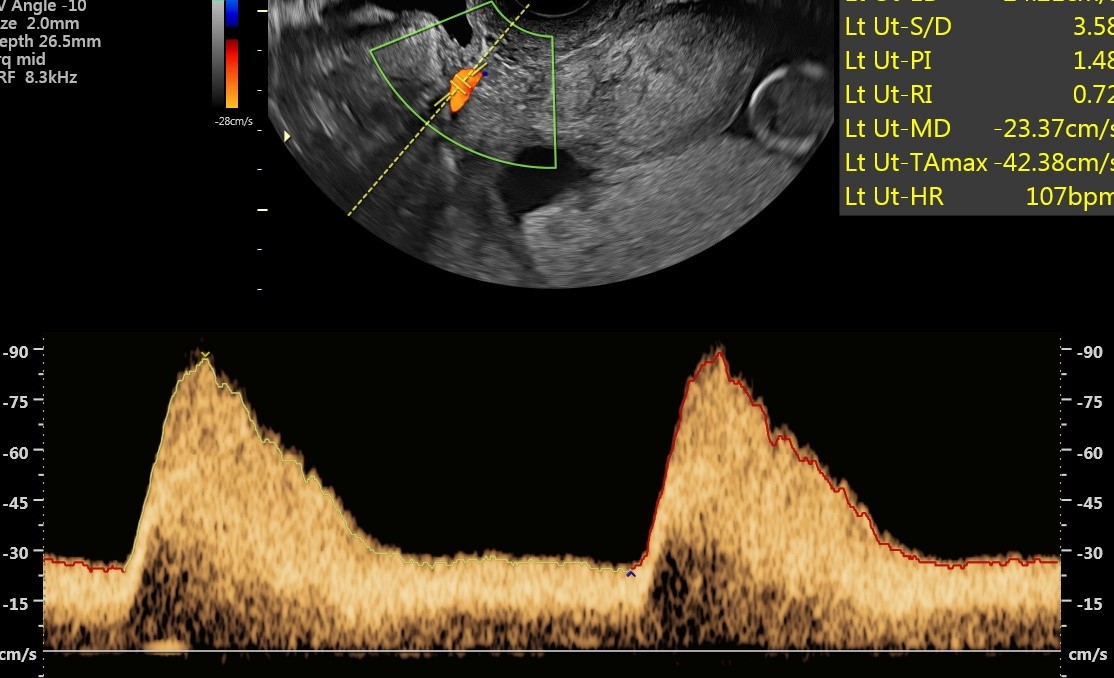

Dzień Zdrowia Aorty - przebadano ponad 40 osób

2022-12-20

Badania przesiewowe aorty organizowane w ramach Dnia Zdrowia Aorty cieszyły się ogromnym zainteresowaniem. Pierwsi chętni do badań ustawili się w kolejce do zapisów już po godz. 8. U żadnej z osób nie wykryto tętniaka. Ta grupa pacjentów może spać spokojnie.

USG Dopplera aorty przeprowadzali dr n. med. Miłosz Kawa i dr n. med. Maciej Wojtuń. Grupą docelową, do której skierowane były badania były osoby po 65. roku życia, u których stwierdzono jednocześnie trzy spośród następujących czynników ryzyka sercowo-naczyniowego: choroba wieńcowa, palenie tytoniu, nadciśnienie tętnicze, hiperlipidemia, płeć męska, występowanie tętniaka aorty brzusznej u rodziców lub rodzeństwa czy przewlekła obturacyjna choroba płuc.